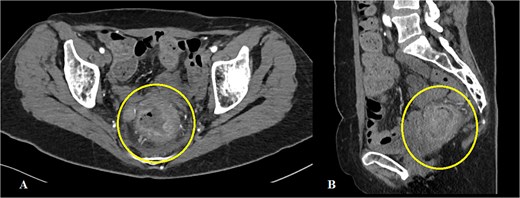

On a digital rectal examination an irregular, rectal mass was palpated. A colonoscopy revealed a large polypoid mass located ⁓5–7 cm from the anal verge, nearly occluding the rectal lumen and demonstrating surface necrosis. The obtained biopsies (standard hematoxylin/eosin stain and immunohistochemistry) confirmed the presence of rectal LMS. Preoperative laboratory findings showed mildly elevated inflammatory markers with a C-reactive protein of 56.4 mg/L and hemoglobin level of 113 g/L, with other parameters within normal range. Abdominal computerized tomography (CT) demonstrated a rectal mass (Fig. 1A and B). The hospital’s oncologic board decision was to start the treatment with upfront surgery. The patient underwent an abdominoperineal rectal resection with total mesorectal excision. The postoperative course was uneventful. The length of hospital stay was 12 days.

Abdominal CT showing a mass in the rectum: (A) axial scan, (B) sagittal scan.